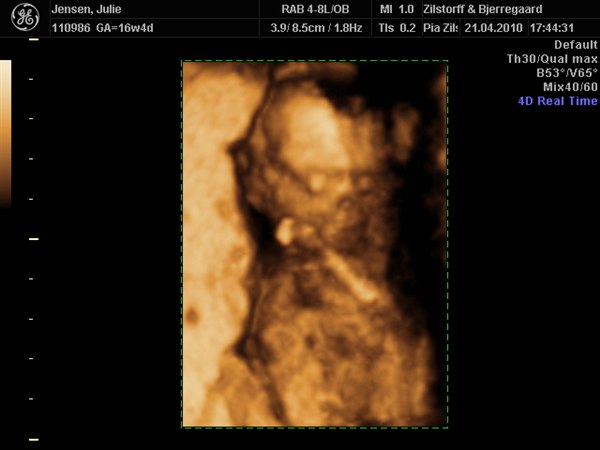

Det var en lille pige der tittede frem på skærmen igår

Desværre var hun en lille puttegøj så der blev ikke rigtig nogle "gode" billeder.... Da hun putter sig godt med moderkagen og den der væg der så hun ligger lige i sådan et hul :) Men har fået tid til i uge 28 igen :) Så ville hun ikke lade mig gå uden et par perfekte billeder :) Smiler....

Her er lidt billeder :)